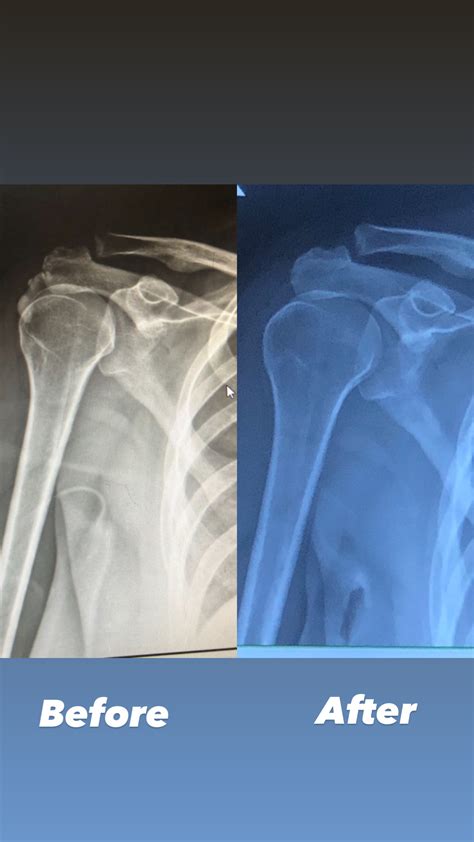

The good news is that most cases of calcium deposits in shoulder can be managed without surgery. Because the body naturally wants to resorb these deposits, treatment usually focuses on managing pain and inflammation until the process is complete.

If conservative treatments fail, medical professionals may suggest more direct interventions, such as barbotage, where the doctor uses a needle to break up the calcium deposit and suction it out. Another option is extracorporeal shockwave therapy (ESWT), which uses sound waves to stimulate the breakdown of the calcification.